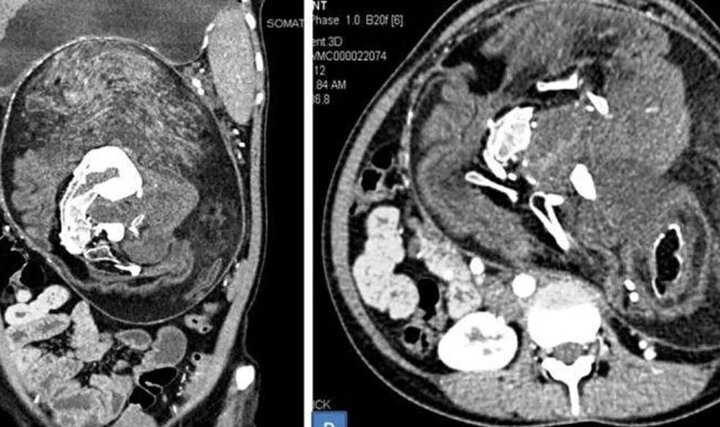

Bụng cô gái ở Ấn Độ cứ to dần dù không ăn nhiều, bác sĩ nghi có khối u, kết quả chụp CT bất ngờ phát hiện bào thai đôi.